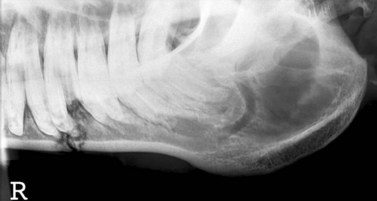

Fractures of the caudal mandible

image

Fig. 9.28 Fracture of horizontal ramus involving a tooth.